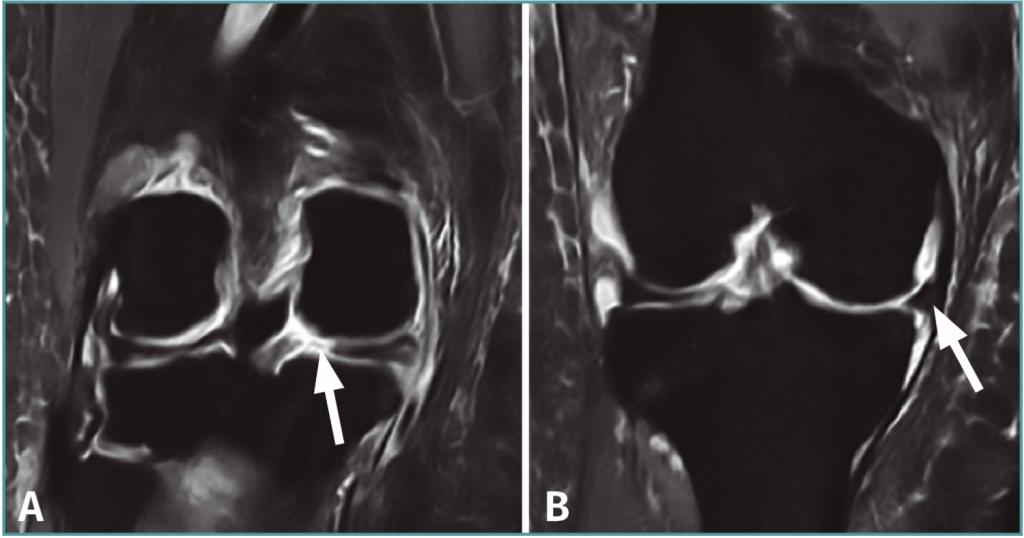

Describe los movimientos de los meniscos hacia la parte anterior, propios del mecanismo de flexo-extensión de la rodilla. Partiendo de una extensión de rodilla, al realizar la flexión los meniscos retrocederán, ya que en muchos casos puede deformarse en su desplazamiento. Hay factores pasivos y activos que influyen en el mismo.

Factores pasivos en donde los meniscos son afectados por los cóndilos femorales, quienes se deslizan y expulsan ante la compresión. Mientras que los Factores Activos los meniscos se deslizan hacia adelante porque los alerones meniscorrotulianos se tensan por el ascenso de la rótula, esto ocurre durante la extensión.

Biomecánica menisco tibial:

Describe los movimientos de rotación axial de los meniscos. En éstos, los meniscos rotarían de la misma manera y en el mismo sentido que lo hacen los cóndilos femorales sobre la meseta tibial. Presentándose dos situaciones: la tibia rota hacia afuera, el menisco interno se desplaza a la parte posterior, y el menisco externo a la parte anterior.

Y si la tibia hace fractura hacia dentro sucede al contrario, el menisco interno se desplazaría hacia la parte anterior y el menisco externo hacia la parte posterior. En cualquiera de los 2 casos los meniscos pueden sufrir deformaciones pues pudiese quedar fijo en la inserción en los cuernos.